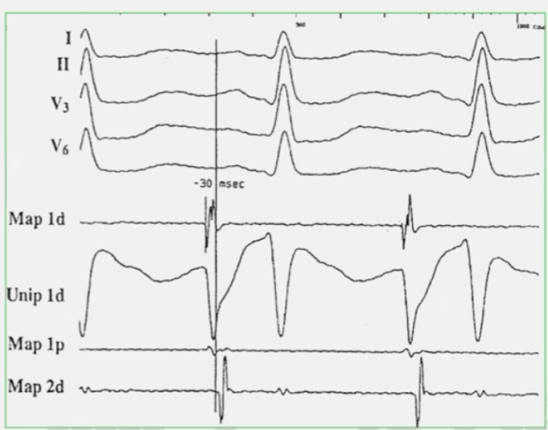

局灶性房速的标测

A-P’40ms的靶点, 并非“最早激动点”,仍需继续标测或试消融证实。

Poty提出结合单极电图QS样A波,确定有效靶点,十分有用。